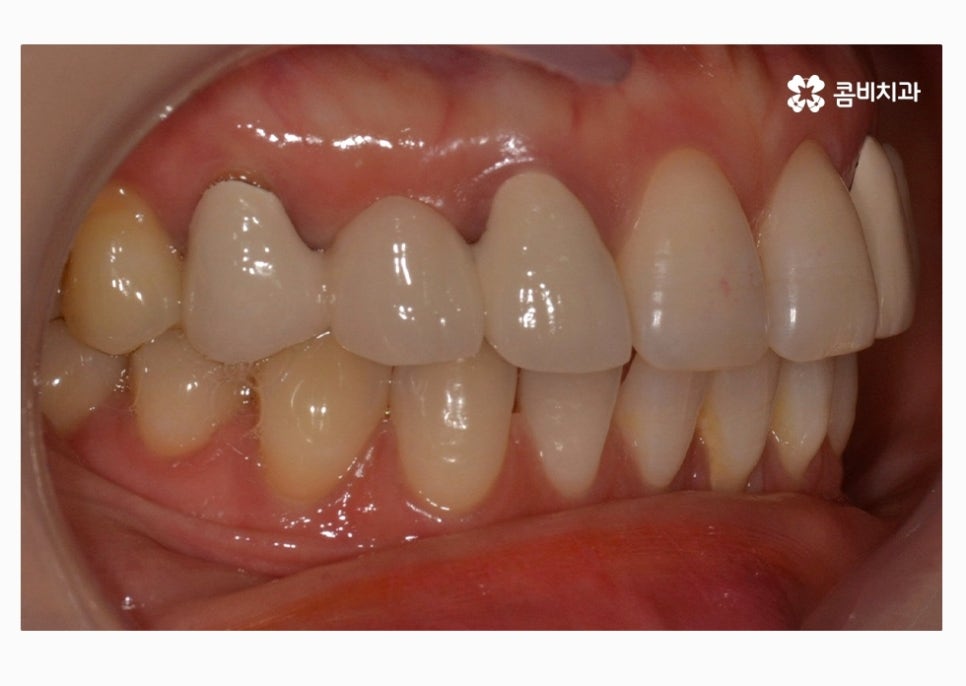

치아교정으로 치열을 가지런하게 하고

30대임플란트 식립까지 잘 마친 상태이며

식립 후에는 골 유착이 튼튼하게 이뤄지는지 기다린 후

주변 치아의 색과 모양에 맞는 보철물을 결합하여

마무리가 된다고 할 수 있어요.